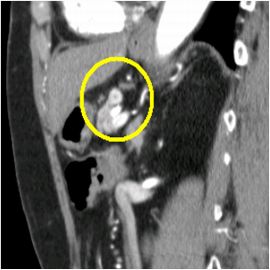

CT検査にて膵体部に腫瘍を認め、精査の結果、膵体部腫瘍疑いと診断し膵体尾部切除術を施行した。

病理診断結果はインスリノーマ(インスリン産生膵島細胞腫)であった。

CT画像